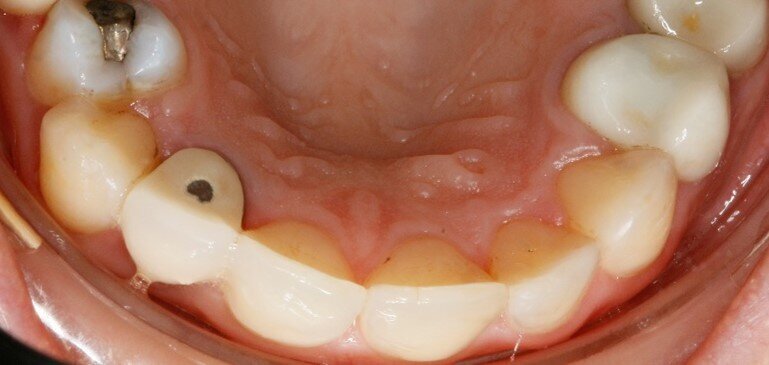

A distanza di sei mesi dalla rimozione dei pigmenti durante la seduta di igiene orale professionale, i siti che presentano black stains sono diminuiti del 53,13%. I pigmenti inoltre hanno iniziato a ripresentarsi, seppur in quantità ridotte, a due mesi dalla seduta di igiene, mentre solitamente la ricomparsa avveniva a distanza di 3-4 settimane (Figg. 4a-4c).

Fig. 4a - Fotografia del secondo sestante palatale al primo rilevo delle black stains.

Fig. 4b - Controllo a tre mesi.

Fig. 4c - Controllo a sei mesi.